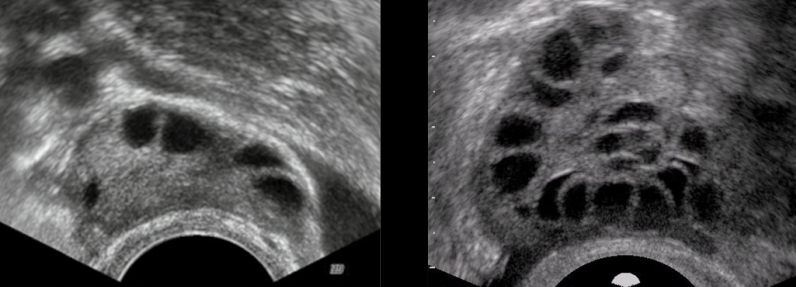

3) 골판초음파에서 다낭성 난소

난소 초음파에서 다수의 미성숙 난포가 보인다.

| 다낭성 난소 (미성숙 난포) | 초음파 검사상 다낭성 난소로 2~9mm 직경의 난포가 12개 이상 난소의 부피가 10cm3 이상 증가되어 있는 것이 특징 (난소 형태 평가하기 위해서 생리 직후에 하는 것이 가장 적절하다) |